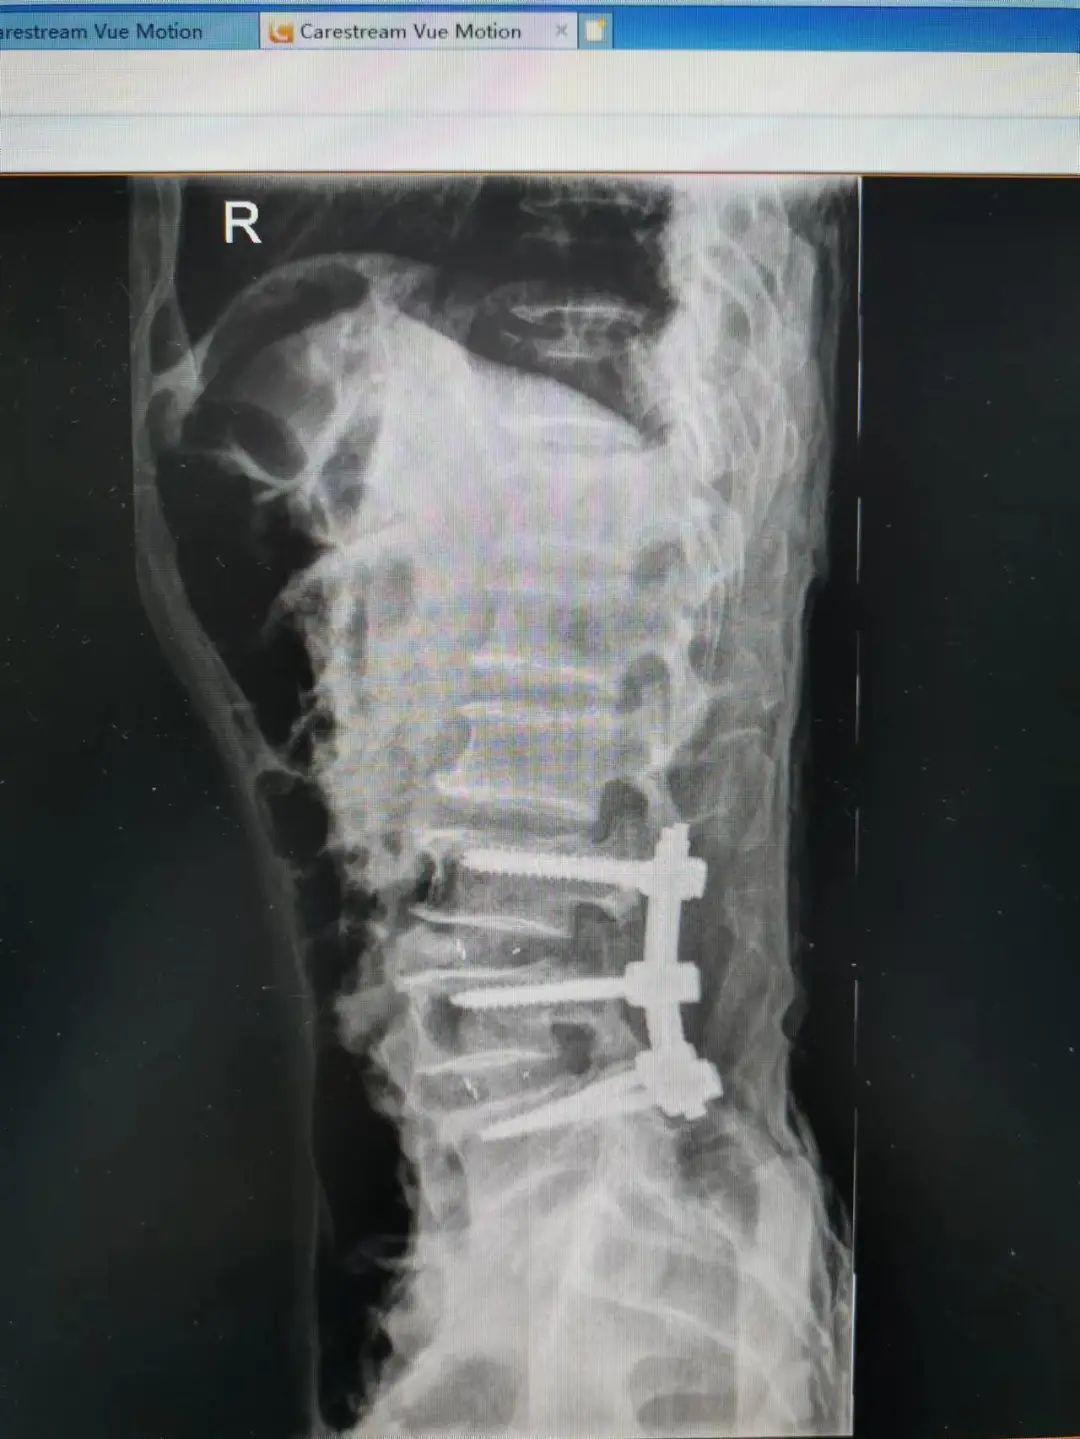

由于楊先生的病情嚴重,需住院治療。楊先生入院后,瀘州市中醫(yī)醫(yī)院骨傷二科科主任楊陳一制定了手術(shù)計劃,決定脊髓型頸椎病的手術(shù)從前路切開減壓,頸3/4 、頸4/5、 頸5/6、 頸6/7椎間盤切除,椎間融合,鋼板內(nèi)固定術(shù)手術(shù),而腰椎管狹窄癥經(jīng)后路切開減壓,腰3/4、腰4/5椎同盤動除,椎間融合、釘棒系統(tǒng)內(nèi)固定術(shù)。

楊先生術(shù)后拍片